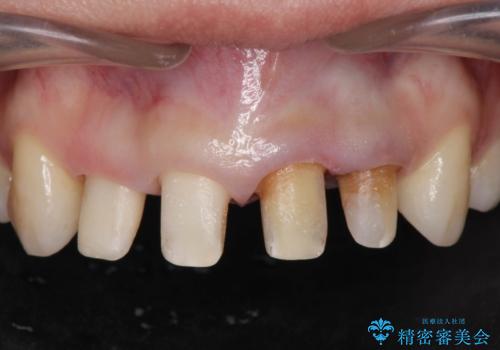

- 神経の死んでしまっている前歯の変色の改善を求めて来院されました。

根管治療をしたのち時間が経過して変色が目立つ歯と、レジン充填が複数箇所に及んでいる歯も同時にオールセラミック治療を行っていくこととなりました。

- 52.8万円(ジルコニアクラウン×4・仮歯×4)費用は治療当時の料金となります